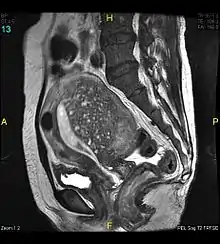

Magnetic resonance imaging

Magnetic resonance imaging (MRI) provides slightly better diagnostic capability compared to TVUS, due to the increased ability of MRI to differentiate objectively between different types of soft tissue.[25] This is possible with MRI's higher spatial and contrast resolution. Overall, it is estimated that MRI has a sensitivity of 74% and specificity of 91% for the detection of adenomyosis.[11] Diagnosis through MRI focuses predominately upon investigating the junctional zone. The uterus will have a thickened junctional zone with darker/diminished signal on both T1 and T2 weighted sequences.[25]

Three objective measures of the junctional zone can be used to diagnose adenomyosis.[25]

- A thickness of the junctional zone greater than 8–12 mm. Less than 8 mm is normal.

- A junctional zone width being greater than 40% of the width of the myometrium.

- Variability in the width of the junctional zone being greater than 5 mm.

Interspersed within the thickened, darker signal of the junctional zone, one will often see foci of hyperintensity (bright spots) on the T2 weighted scans representing small cystically dilatated glands or more acute sites of microhemorrhage.[25]

MRI is limited by other factors, but not by calcified uterine fibroids (as is ultrasound). In particular, MRI is better able to differentiate adenomyosis from multiple small uterine fibroids.